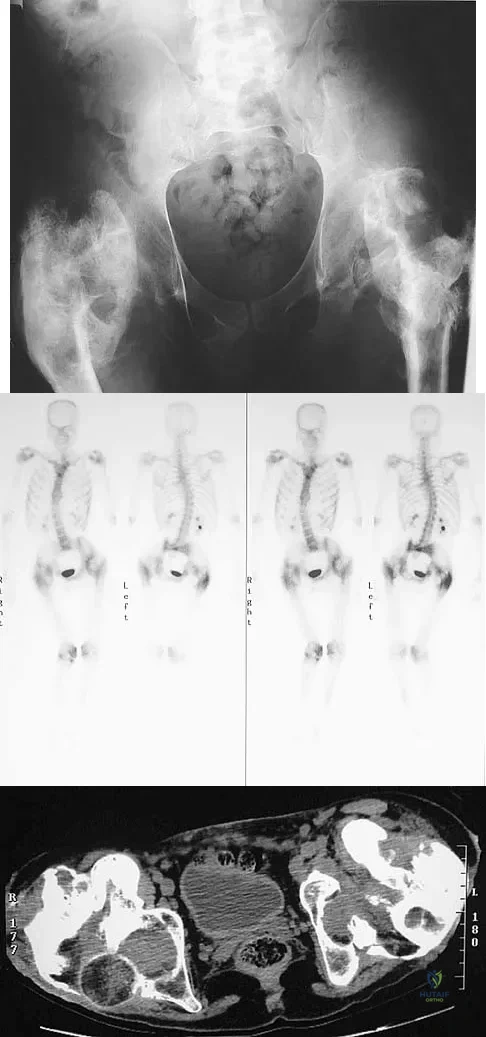

Figure 11a shows the AP pelvis radiograph of a 25-year-old man who sustained a spinal cord injury 10 years ago. A bone scan and a CT scan are shown in Figures 11b and 11c. To prevent recurrence after resection, management should consist of